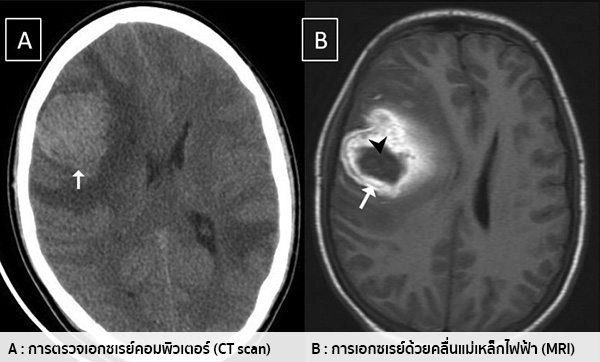

อาการของโรคมะเร็งสมองจะขึ้นอยู่กับขนาด และตำแหน่งที่พบของเนื้องอก โดยอาการที่พบ อาจมีสาเหตุหรือเป็นผลข้างเคียง มาจากความผิดปกติอื่น ที่ไม่ใช่มะเร็งสมองก็ได้ ไม่ควรวิตกกังวลจนเกินไป หากเป็นเพียงอาการเบื้องต้น หรืออาการที่ไม่รุนแรง แต่ก็สามารถไปพบแพทย์ได้ หากมีข้อสงสัย โดยทั่วไปแล้ว ผู้ที่เป็นโรคมะเร็งสมอง อาจมีอาการดังต่อไปนี้